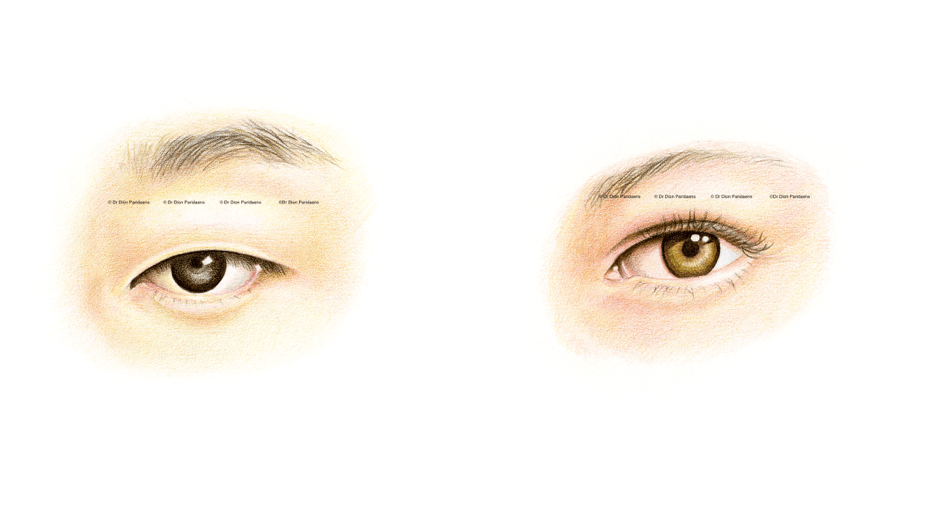

Anatomically speaking, there are a number of subtle differences in the upper eyelids of East Asians compared to the eyelids of Europeans and Sub-Saharan Africans. While some East Asians have an eyelid crease and some do not, there is also a large variation in the skin fold position of the upper eyelid in East Asia. The position of the upper eyelid skin fold can vary from 1 mm above the lash line to approximately 10 mm, but when people come to the ELZA Institute for oculoplastic surgery, the changes they desire is very individual, but usually the goal is to obtain a more energetic, youthful and natural look.

The most commonly performed eyelid surgery in people from East Asia is sometimes referred to as “double eyelid surgery”, and is a cosmetic surgical method that reconstructs the skin of the upper eyelid. Often oculoplastic surgeons also partially remove any skin surplus, which is a natural consequence of ageing. We oculoplastic surgeons can also create an eyelid crease – something that is naturally missing in people from East Asia (which is sometimes referred to as a “mono-lid”).

Postoperative image.